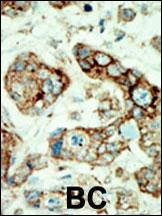

Formalin-fixed and paraffin-embedded human cancer tissue reacted with the primary antibody, which was peroxidase-conjugated to the secondary antibody, followed by AEC staining. This data demonstrates the use of this antibody for immunohistochemistry; clinical relevance has not been evaluated. BC = breast carcinoma; HC = hepatocarcinoma.